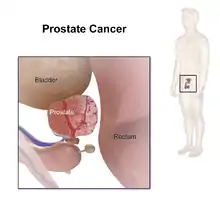

Pathophysiology

The prostate is part of the male reproductive system that helps make and store seminal fluid. In adult men, a typical prostate is about 3 cm long and weighs about 20 g.[57] It is located in the pelvis, under the urinary bladder and in front of the rectum. The prostate surrounds part of the urethra, the tube that carries urine from the bladder during urination and semen during ejaculation.[58] The prostate contains many small glands, which make about 20% of the fluid constituting semen.[59]

Superiorly, the prostate base is contiguous with the bladder outlet. Inferiorly, the prostate's apex heads in the direction of the urogenital diaphragm, which is pointed anterio-inferiorly. The prostate can be divided into four anatomic spaces: peripheral, central, transitional, and anterior fibromuscular stroma.[60] The peripheral space contains the posterior and lateral portions of the prostate, as well as the inferior portions of the prostate. The central space contains the superior portion of the prostate including the most proximal aspects of the urethra and bladder neck. The transitional space is located just anterior to the central space and includes urethra distal to the central gland urethra. The neurovascular bundles course along the posterolateral prostate surface and penetrate the prostatic capsule there as well.

Because of the prostate's location, prostate diseases often affect urination, ejaculation, and rarely defecation. In prostate cancer, the cells of these glands mutate into cancer cells.

Eventually, the tumor may grow large enough to invade nearby organs such as the seminal vesicles or the rectum, or tumor cells may develop the ability to travel in the bloodstream and lymphatic system.

Prostate cancer is considered a malignant tumor because it can invade other areas of the body. This invasion is called metastasis. Prostate cancer most commonly metastasizes to the bones and lymph nodes, and may invade the rectum, bladder, and lower ureters after local progression. The route of metastasis to bone is thought to be venous, as the prostatic venous plexus draining the prostate connects with the vertebral veins.[63]